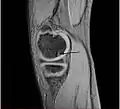

Sagittal MRI: Linear low T1 signal at the articular surfaces of the lateral aspects of the medial condyle of the femur confirms the presence of OCD.